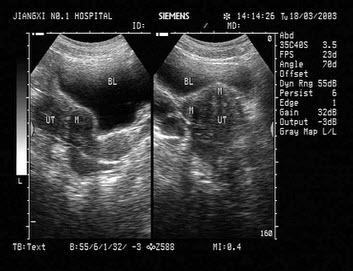

女性,43岁,因月经量多,经期时间长,月经周期短就诊。体检:子宫体积大,表面不平整。结合超声图像,最可能的诊断为()

[案例分析题] 病历摘要:女性,48岁,因月经周期缩短,经期延长及经量增多1年就诊。患者既往月经正常,3~4/30天,经量中等,无痛经。近一年来月经周期缩短,经期延长,7/24天,经量明显增多,不伴痛经。G2P2,均为足月顺产。带环已15年。妇科检查:外阴(-),阴道(-),宫颈光滑,子宫如孕12周大小,表面凸凹不平,质硬,无压痛,双侧附件(-)。实验室检查:WBC6.8×109/L,Hb85g/L,PLT190×109/L。

[试题]女性,40岁。月经周期缩短,经期延长,经量增多1年。患者1年来月经周期缩短,经期延长,7~8/24~25天,经量明显增多,不伴痛经。白带正常。既往月经正常,3~4/30天,经量中等,无痛经。生育史:孕产,足月顺产,放置宫内节育器8年。查体:T36.7℃,P86次/分,R18次/分,BP100/70mmHg。贫血貌。心肺检查未见异常。肝脾肋下未触及。妇科检查:外阴已产式,阴道光滑通畅,宫颈光滑;宫体如11周妊娠大,表面凹凸不平、质硬、活动度较差;双附件(-)。实验室检查:血常规:Hb65g/L,MC

[案例分析题] 女性,40岁。月经周期缩短,经期延长,经量增多1年。患者1年来月经周期缩短,经期延长,7~8/24~25天,经量明显增多,不伴痛经。白带正常。既往月经正常,3~4/30天,经量中等,无痛经。生育史:孕3产1,足月顺产,放置宫内节育器8年。查体:T36.7℃,P86次/分,R18次/分,BP100/70mmHg。贫血貌。心肺检查未见异常。肝脾肋下未触及。妇科检查:外阴已产式,阴道光滑通畅,宫颈光滑;宫体如11周妊娠大,表面凹凸不平、质硬、活动度较差;双附件(-)。实验室检查:血常规:Hb65